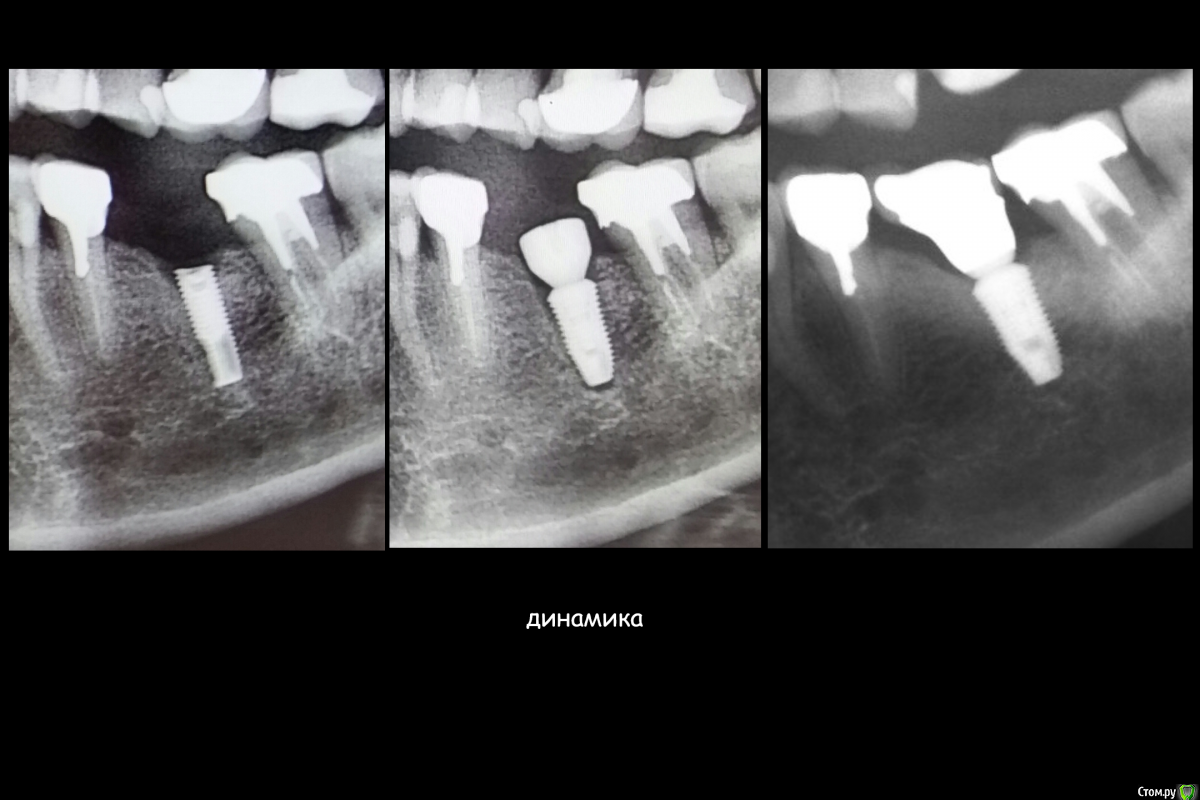

Этот имплантат, можно было лечить!!!!!!